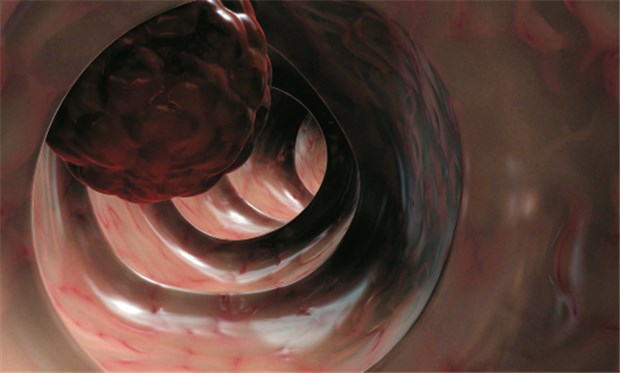

ASS schützte Patienten mit Lynch-Syndrom vor Darmkrebs, selbst lange, nachdem sie die Einnahme beendet hatten.

© Foto: Sebastian Kaulitzkiwww.fotolia.de